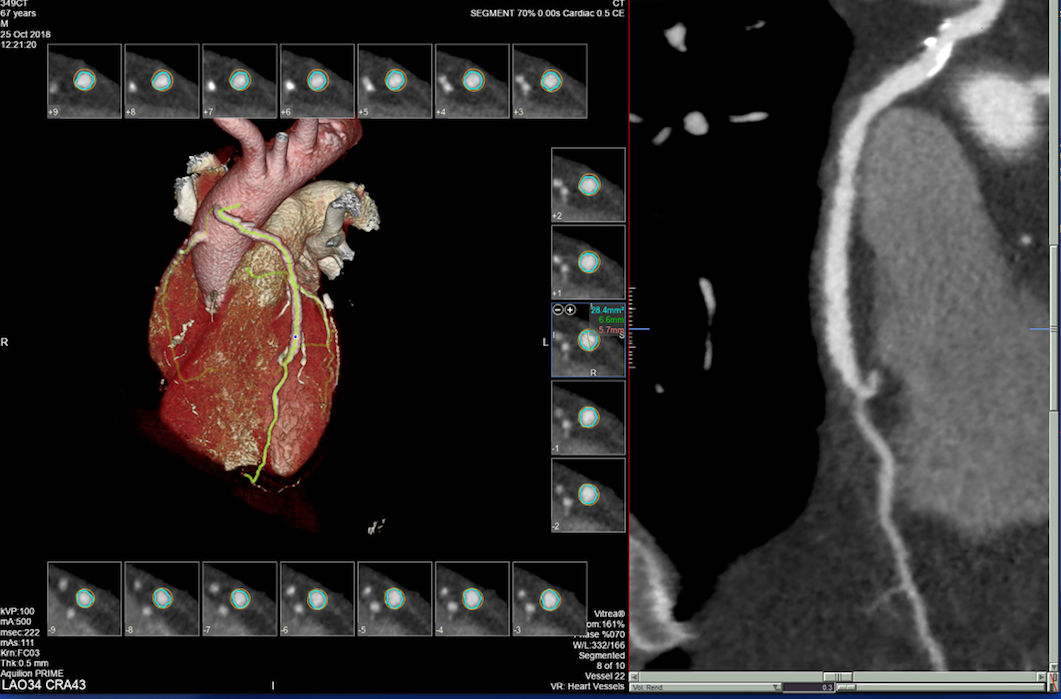

Također u slučaju pojave boli u prsima, gdje nema EKG promjena i lab.nalazi su uredni, radi se takozvani «triple rule-out» CT koronarografija-da bi se jednim pregledom isključila bolest koronarnih arterija, plućna tromboembolija ili disekcija aneurizme aorte, od kojih je svaka ponaosob potencijalno fatalna.

- MSCT koronarografija (prikaz krvnih žila srca CT-om, bez neugodnosti i komplikacija koje nosi klasična koronarografija), u saradnji s Poliklinkom dr.Al-Tawil